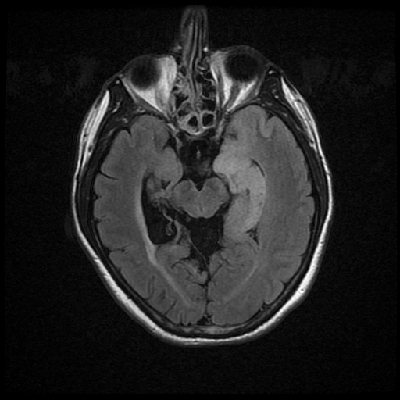

Neurologic and mental examination showed intact immediate memory but inability to recall 3 objects in 5 minutes. He was not oriented to time or space or situation but oriented to person. His remote memory was intact. There was left superior quadrantonopsia but no focal motor or sensory deficits. FLAIR images on MRI showed a lesion in the left mesial temporal lobe (Panel 1). This lesion had increased T2 signal but without enhancement on T1 images. This lesion also had mass-effect and edema within that region. On FLAIR images, there were some small foci of abnormal signal in the white matter of the right parietal lobe (Panel 2) but these foci did not enhance (Panel 3). There is a vague, poorly demarcated, triangular shaped periventricular signal abnormality in the left parietal lobe (Panel 2) but this area did not enhance (Panel 3). On another image (obtained higher to Panel 2 and 3), however, there is a small cluster of enhancing spotty signal in the white matter of the left parietal lobe (Panel 4) and the largest focus is about 0.4 cm in diameter. There were areas with features of encephalomalacia in his right mesial temporal lobe that would be explained by his history of prior infarct.

2. FLAIR |